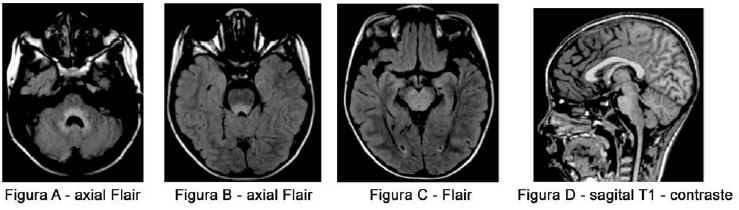

paciente de 7 anos, com náuseas, vômitos e febre de início agudo, evoluindo com queda do nível de consciência, foi submetido à ressonância magnética. Analise as imagens a seguir:

Assinale a alternativa que contém o diagnóstico provável.